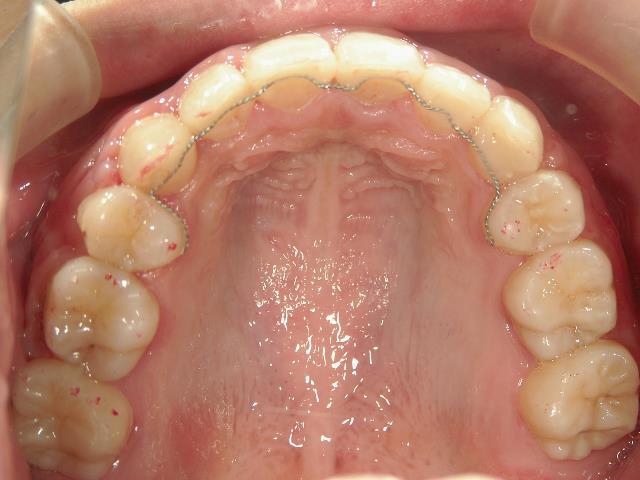

矯正歯科 治療前 左右上下4番  計4本抜歯

矯正_灰色.pngno.18_2196_治療前_上.jpg矯正_灰色.png

矯正_灰色.pngno.18_2196_治療後_上.jpg矯正_灰色.png